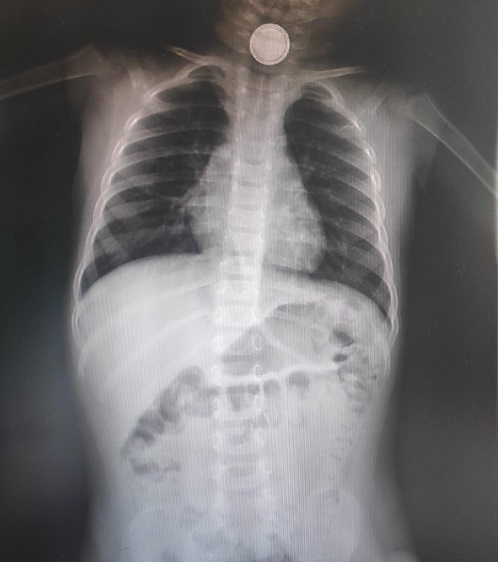

En la exploración física destaca sialorrea significativa sin signos de dificultad respiratoria, auscultación cardiopulmonar normal, sin otros síntomas asociados. Constantes normales. Se realiza una radiografía de tórax-abdomen (Figura 1) visualizándose pila de botón en tercio superior de esófago. Se procede a extracción urgente de cuerpo extraño en el quirófano bajo guía broncoscópica y se realiza esofagograma en el que se observa quemadura esofágica grado II secundaria.

Figura 1. Radiografía tórax-abdomen